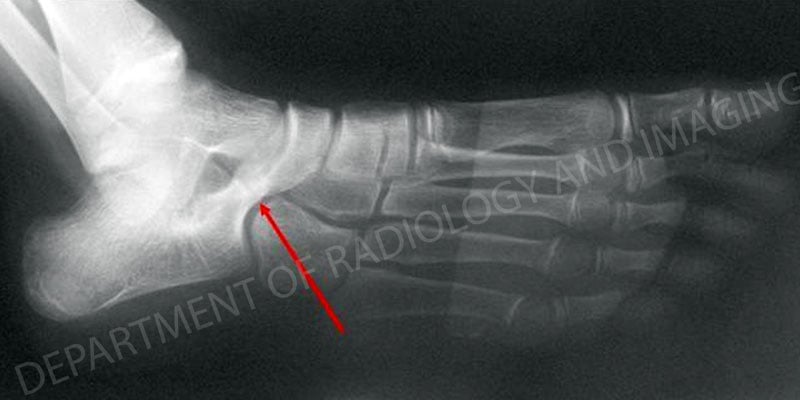

Most tarsal coalitions may be classified as one of two types: a calcaneonavicular coalition, in which the tissue develops between the calcaneus (heel bone) and the navicular (one of the foot bones), or a talocalcaneal or subtalar coalition, in which the coalition develops between the calcaneus and the talus (the ankle bone). The coalition may be composed exclusively of bone, a combination of bone and cartilage, or even fibrous tissue. Tarsal coalitions occur in both feet in about half of all cases.

Right foot with calcaneonavicular coalition. The red arrow indicates the coalition.

Initial treatment for tarsal coalitions is non-operative; the patient is required to rest or immobilize the foot. Although pain relief can be achieved in this way, in many cases the result is only temporary. Non-operative treatment can be appropriate for patients with tarsal coalitions that are symptom-free, and whose condition only becomes apparent on x-ray taken incidentally for another condition, such as an acute ankle sprain.